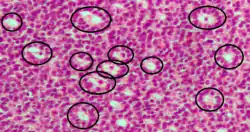

Call–Exner bodies marked with black circles in an intermediate-high magnification micrograph of a granulosa cell tumour, a type of sex cord stromal tumour. H&E stain.

Call–Exner bodies, giving a follicle-like appearance, are small eosinophilic fluid-filled punched out spaces between granulosa cells.[1] The granulosa cells are usually arranged haphazardly around the space.

They are pathognomonic for granulosa cell tumors.